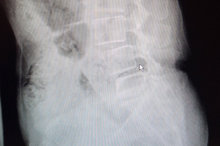

術後腰椎突出改善(童綜合醫院提供)

黃姓婦人經朋友介紹到童綜合醫院微創中心接受治療,副院長徐少克確認患者因體重過重導致腰部支撐力不足,腰椎長期支撐過重之下,導致腰椎第三、第四與第五節椎間盤突出合併脊椎移位;安排住院進行腰椎微創融合手術,術後患者住院5天即出院返家休養,目前大腿麻痛情形改善,也不再受失眠所苦,恢復以前健康時的日常生活作息,因此也願意和家人一同出遊。